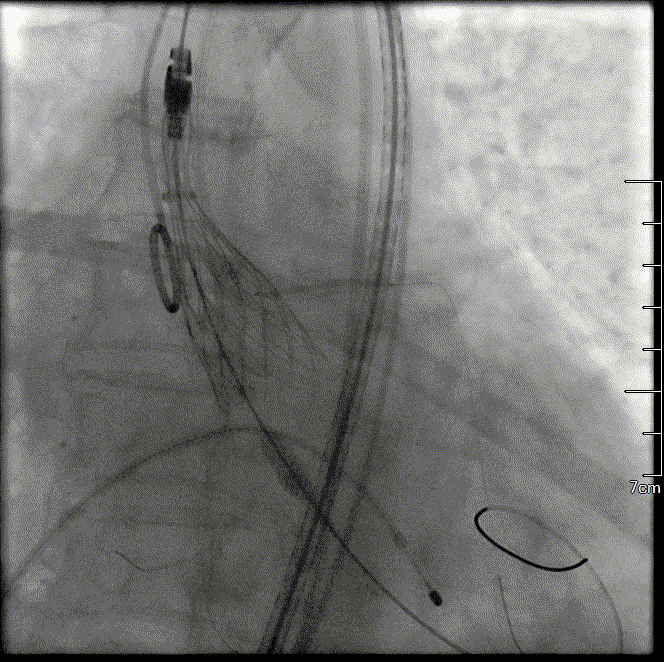

瓣膜完全释放形态良好

工作钢丝送入左室进行起搏,180bpm起搏下预扩张主动脉瓣,完全扩张后,主动脉根部造影无反流,回撤球囊停止临时起搏。